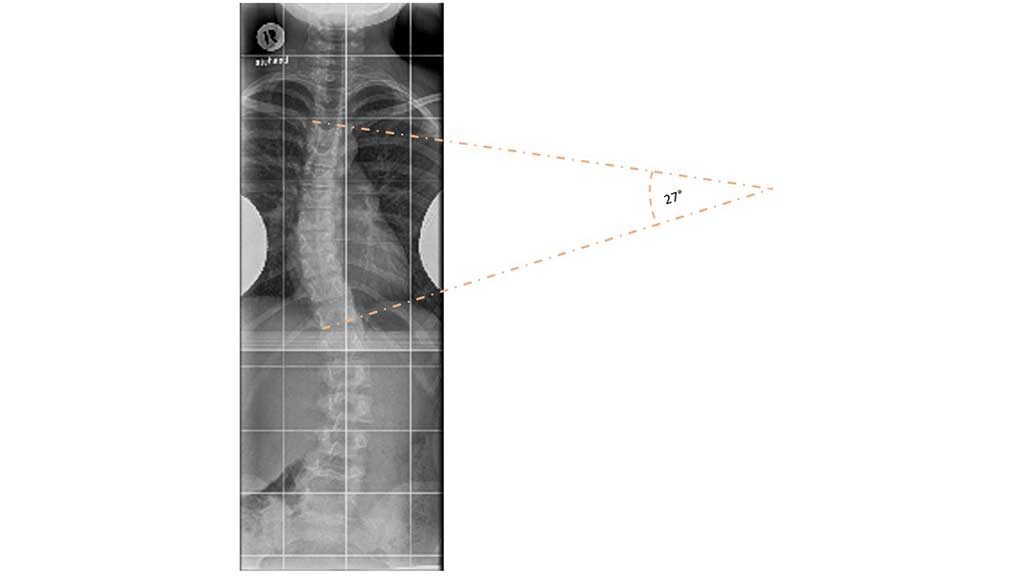

Nach sorgfältiger klinischer Untersuchung sollten im Rahmen der Primärdiagnostik Wirbelsäulenganzaufnahmen in zwei Ebenen im Stehen angefertigt werden. Wenn für die Therapieplanung relevant, kann die Aufnahme in der Frontalebene ebenfalls die Beckenkämme mit ablichten, um hieraus Rückschlüsse auf das Skelettalter zu bekommen. Dabei beschreibt das sogenannte Risser-Stadium den Status der Beckenkammapophyse in Bezug auf ihre Verknöcherung. Das Ausmaß der Skoliose wird über die Winkelmessung nach Cobb bestimmt. Dabei werden die beiden am stärksten verkippten Wirbel oberhalb und unterhalb eines Wirbelsäulenbogens als Neutralwirbel bestimmt. Der Winkel zwischen den beiden Neutralwirbeln wird über Tangenten gemessen (Abb. 1). Die Rotationskomponente wird nach Nash und Moe entsprechend der Position der Bogenwurzeln in der Darstellung des Wirbelkörpers bestimmt.

Der durchschnittliche Cobb-Winkel vor der Behandlung betrug 28,39° ± 9,44°; zum Abschluss der Behandlung lag er bei 27,70° ± 12,34°. Eine Stabilisierung des Cobb-Winkels mit einer Progredienz von ≤ 5° wurde bei 136 (85,5 %) der insgesamt 159 Patienten erzielt. Lediglich bei 23 Patienten aus dem Kollektiv kam es zu einer Progredienz des Cobb-Winkels von mehr als 5°; davon mussten sich 19 Patienten einer Operation unterziehen. Eine Verbesserung des Cobb-Winkels konnte mit einer Abnahme um ≥ 6° bei Abschluss der Behandlung bei 42 Patienten dokumentiert werden (25,4 %). Aus dieser Gruppe wiederum wurde bei 9 Patienten sogar eine Verbesserung des Cobb-Winkels um ≥ 10° erzielt (5,6 % des Gesamtkollektivs).